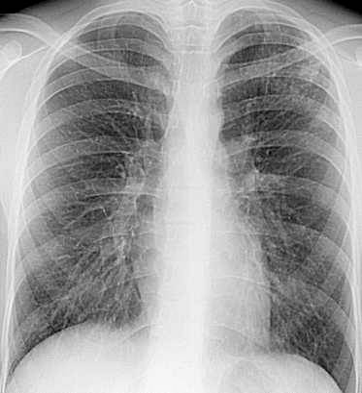

Рис. 4 Рентгенограмма ОГК и схема к ней левого легкого.

В апикальном отделе S1–2 левого легкого определяется обогащенный легочный рисунок за счет множественных полиморфных преимущественно среднеочаговых теней, склонных к слиянию с нечеткими контурами; здесь же имеются плевроапикальные наслоения. Корни легких структурны, не расширены. Купол диафрагмы четкий, синусы свободны.

Заключение: Очаговый туберкулез в S1–2 левого легкого в стадии инфильтрации.